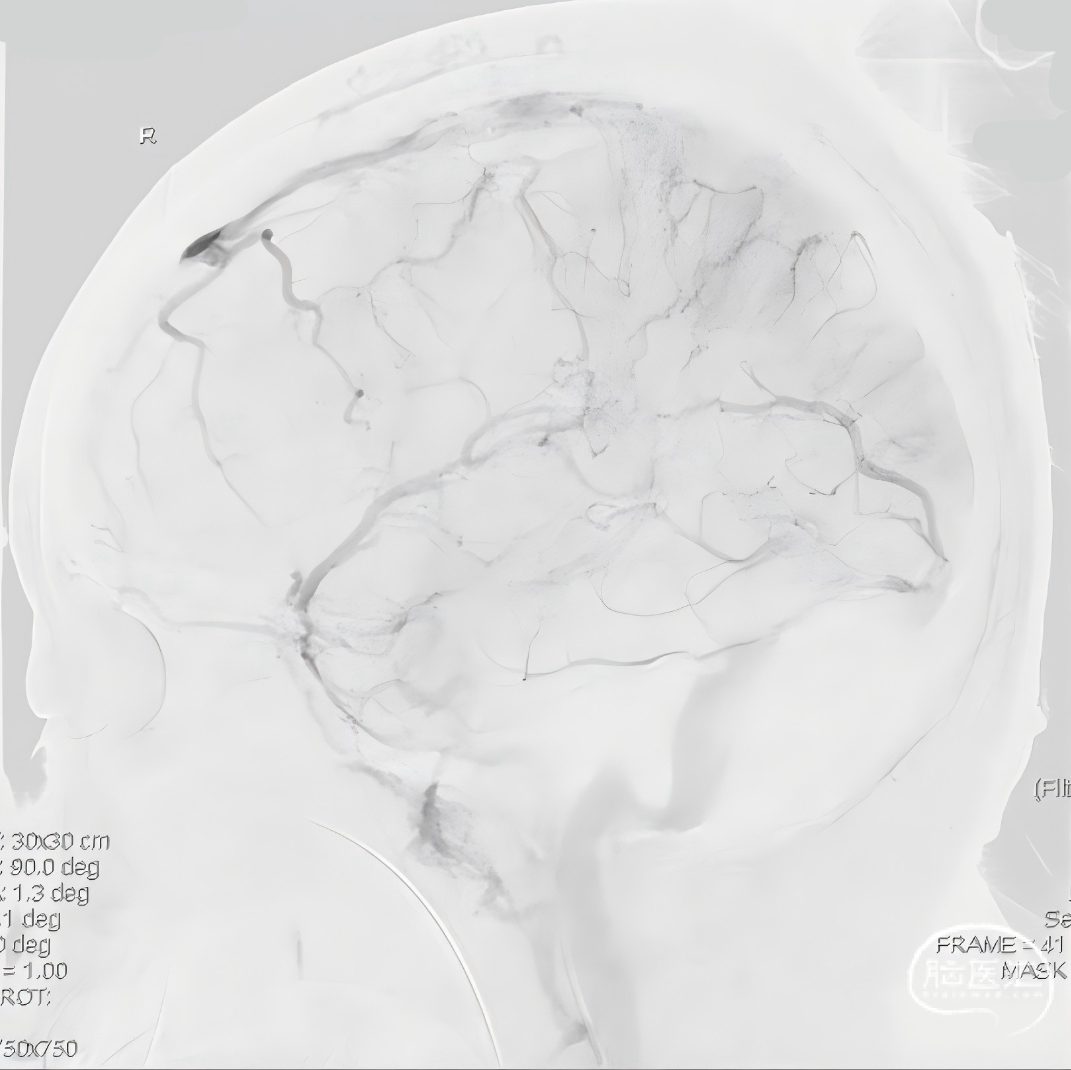

经中间管手推造影,确认血栓位置。

反复抽吸,多次中间管于负压状态下无回血时,负压状态撤出体外,可见大量血栓。

球扩后造影,上矢状窦接触溶栓尿激酶20万U。

球囊扩张和接触溶栓后,再次经中间管反复抽吸后复查造影。

再次给予尿激酶10万U后复查造影。